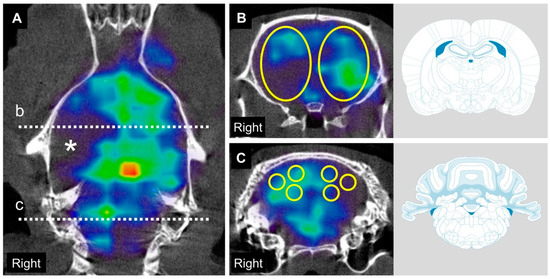

2.2. Time Course of CBF and CbBF after MCAO

4.5. Blood Flow Assessment Using SPECT